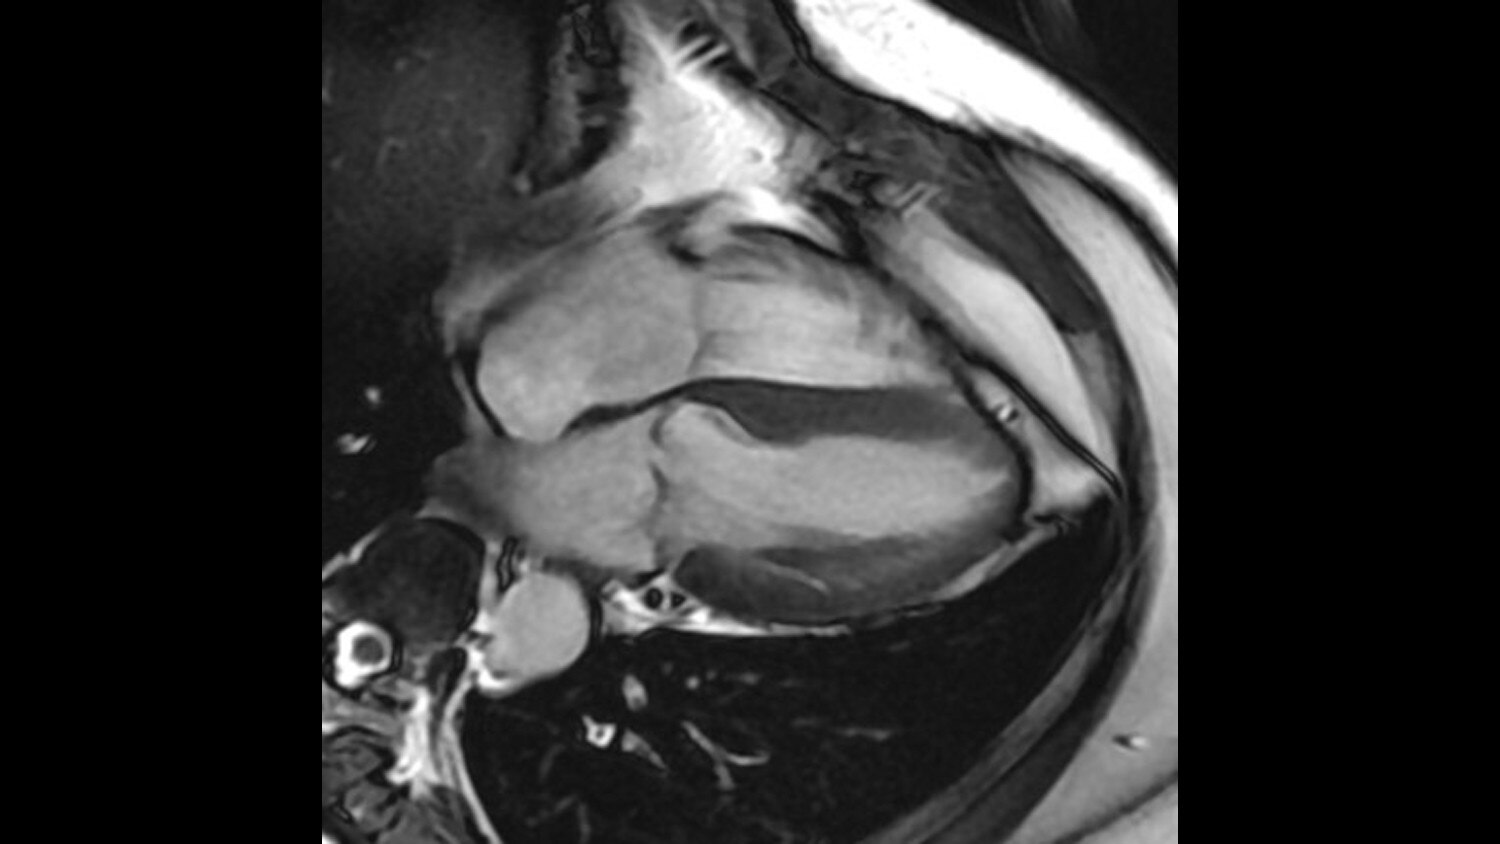

See how the Discovery MR750w gives you the experience you deserve, the performance you desire and the versatility you demand.

Its full 3.0T magnet and 70 cm bore work together to generate extraordinary image quality without compromises. The result for clinicians is new levels of diagnostic performance.

A large usable field of view is needed to properly image off-center anatomy such as a shoulder or hip. So the Discovery* MR750w features a 70 cm flared, open bore design with a large 50 x 50 x 50 cm field of view.

Gradients and RF body coils are water and air-cooled for optimum duty-cycle performance, short repetition time (TR) and echo time (TE), producing sharp and clear images.